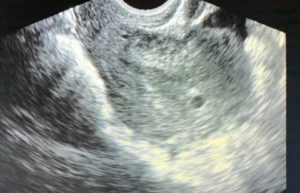

На 10-14 неделе беременности женщина проходит ультразвуковое исследование, позволяющее врачу сделать замеры плодного яйца для установления точного срока гестации. Иногда в ходе обследования обнаруживается деформированное плодное яйцо. Основной причиной этой патологии считается повышение тонуса матки.

При нормальном наступлении беременности околоплодное яйцо располагается в матке. На маленьком сроке, в 5-6 недель оно становится округлым или каплевидным. К 6-7 неделям на продольном скане УЗИ яйцо выглядит овальным, а на поперечном сохраняет округлость. Если же обследование показывает приплюснутость плодного яйца по бокам и отсутствие овальной формы, значит матка находится в тонусе.

Чем может грозить изменение форм и размеров околоплодного яйца? Сильное превышение или уменьшение его размеров свидетельствует о замирании беременности, но, как правило, врач продолжает наблюдения, контролируя динамику развития изменений. О замершей беременности говорит и вытянутое плодное яйцо.

При увеличении тонуса матки углы оболочки яйца выглядят неровными. В большинстве случаев врачи считают такие изменения безобидными, если только они не сопровождаются раскрытием шейки, темными выделениями и болями. При подобных симптомах появляется реальная угроза потери плода.